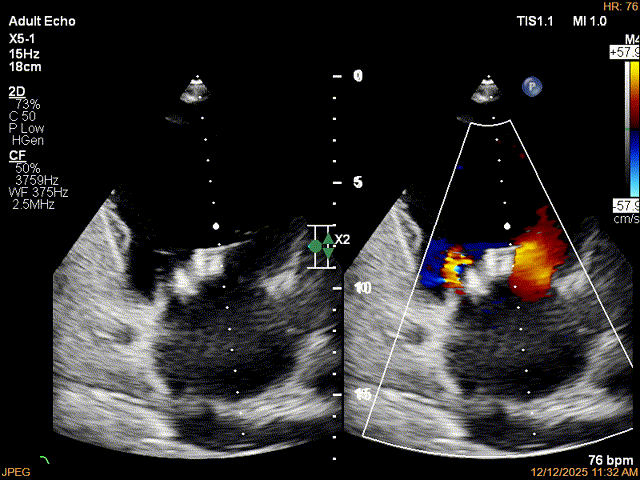

彩色多普勒显示反流明显减少

Multivue下进一步确认后叶夹合量足够

Multivue下植入第二枚XTR

Multivue下调整位置,尽可能多的捕捞脱垂的后叶

第二枚XTR捕获后评估,获得可捕获瓣叶的最大夹合量

第二枚XTR植入后瓣口平均压差3mmHg

3D-Zoom下观察组织桥稳定,内侧残余脱垂

超声评估后决定释放第二枚夹子,继续在其内侧植入第三枚XTR

Multivue下平行植入第三枚夹子

Multivue下抓捕瓣叶,获得充足瓣叶夹合量

捕获后反流降至轻度

第3枚XTR夹合器植入后,跨瓣平均压差为3mmHg